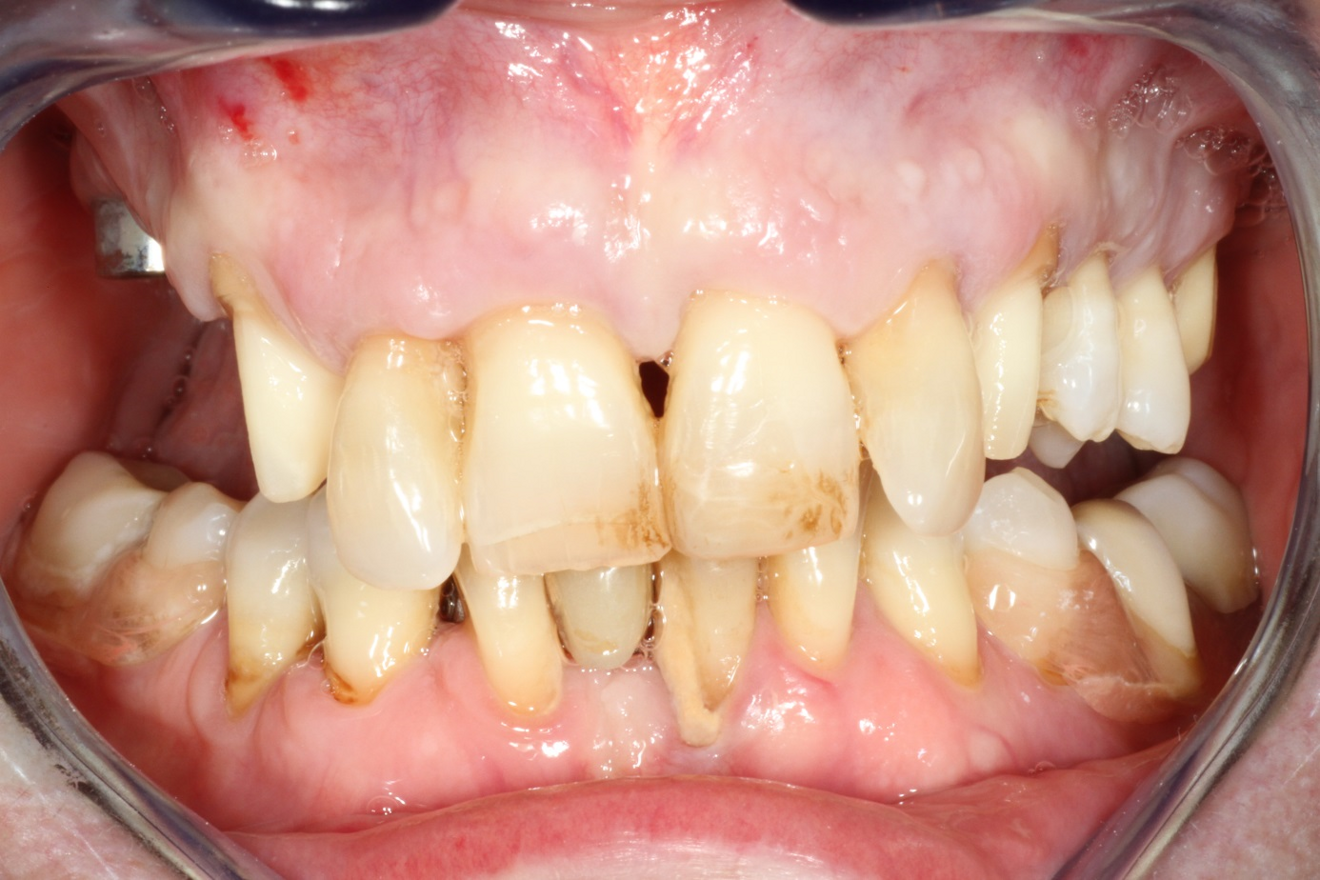

The 58-year-old, non-smoking and systemically healthy female patient was referred by her dentist to our dental clinic for implant treatment. The patient’s main complaints were poor aesthetics in the upper jaw, including a high smile line and distinct tooth pattern anomalies in the anterior maxilla (Figs. 1 & 2), as well as masticatory discomfort. Teeth #17, 15 and 27 were missing and had not undergone any prosthetic treatment, whereas the five missing teeth in the premolar and molar areas on both sides of the mandible had been replaced with a removable partial denture. All remaining teeth were affected by Stage IV periodontitis according to the 2017 Classification of Periodontal and Peri‐implant Diseases and Conditions, displaying a mean periodontal pocket depth of 5.6 mm.7 Mean bleeding on probing and mean plaque index were 70% and 80%, respectively. With respect to periodontal parameters, as well as to oral hygiene measures (visible calculus and dental plaque), the patient’s oral hygiene was graded as poor. The patient had been treated elsewhere with two implants in the posterior maxilla in order to replace the right first premolar and first molar (Fig. 3). She had a thick flat biotype, according to a definition introduced in 1977.8, 9

After obtaining informed consent from the patient, we would start dental rehabilitation in the maxilla, and we opted for a two-stage surgical approach after initial therapy. Initial therapy would consist of systematic periodontal treatment and regular recalls with instructions and checks for dental hygiene over a period of three months. The first stage of rehabilitation of the maxilla would consist of partial extraction therapy in conjunction with Type 1 implant placement in the regions of the teeth #12 and 22 according to the Proceedings of the Fourth ITI Consensus Conference and ridge preservation in the region of teeth #24 and 25 with particulate dentine, obtained and processed from the two extracted left maxillary premolar teeth.10 Owing to increased tooth mobility and the obvious poor buccal bone volume, as displayed on the CBCT scan (CRANEX 3D Ceph, Soredex, KaVo Kerr), regions #11 and 21 were not suitable for the socket shield technique in conjunction with implant placement (Fig. 4). Both central incisors were to be treated with the submerged root technique instead, in order to prevent damage of the buccal socket wall and volume loss of the alveolar ridge after tooth extraction. With both roots in place, a physiological pontic site development for the definitive restoration would be enabled. Based on periodontal re-evaluation after the initial therapy, only the two maxillary canines were considered worth preserving. The left first molar was to be temporarily retained in order to serve, in conjunction with the two canines, as an additional abutment tooth for fixation of the temporary bridge during the healing period. Crown preparation of the three remaining teeth would be done before surgical treatment, in order to prefabricate a temporary bridge for immediate fixed provisionalisation after the first surgery. The second surgical stage would consist ofimplant placement in region #24, performing of the socket shield technique on the mesiobuccal root, submersion of the distobuccal root and extraction of the palatal root of tooth #26 before immediate implant placement. Definitive prosthetic treatment would be performed after a transgingival implant healing period of at least three months, applying a conventional implant loading protocol with fixed bridges.11